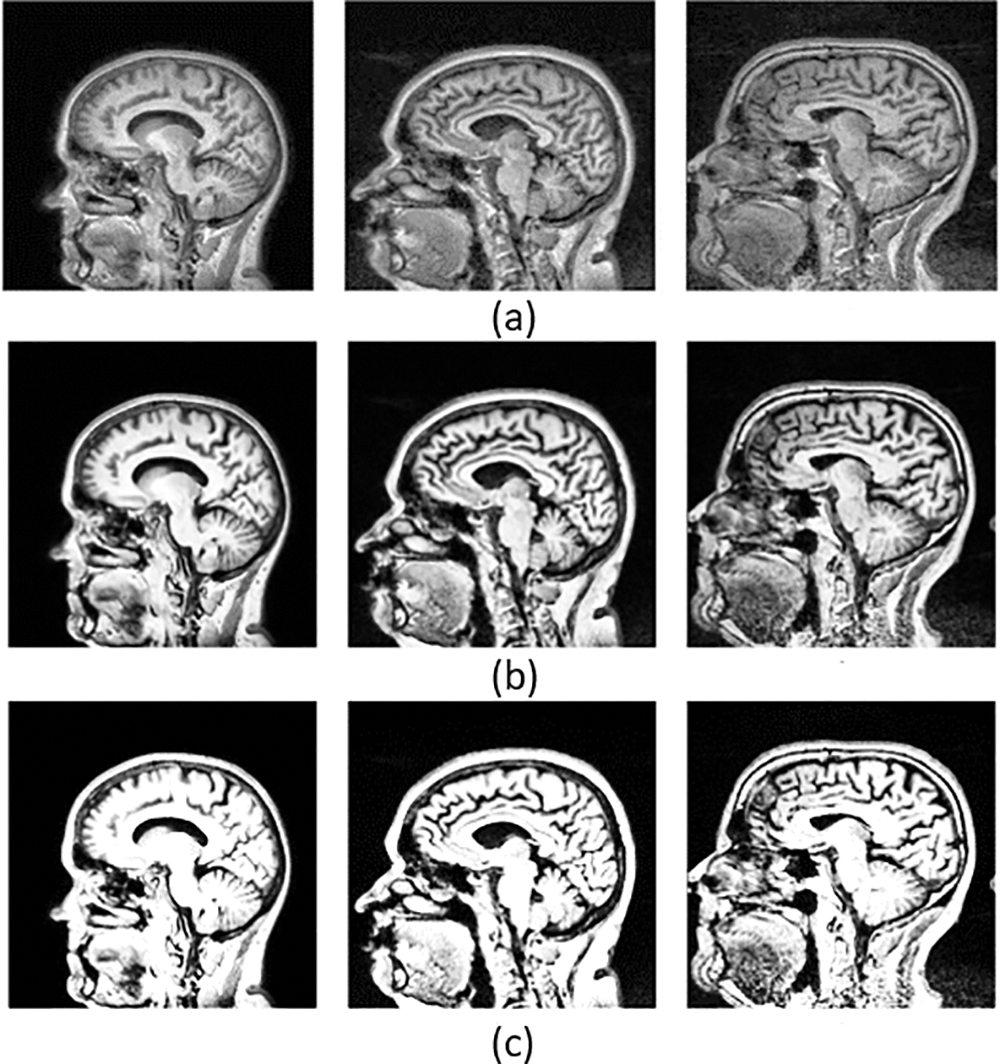

Alzheimer’s Disease (AD) is the most debilitating brain disease affecting any age, especially the elderly. A condition undertreated and under-recognized is becoming a serious public health concern. Alzheimer’s Disease (AD) is a significant public health problem impacting life expectancy. AD was first identified in 1906 by Alois Alzheimer, who employed memory loss, pathology indications, and disorientation as diagnostic criteria [1]. AD can express itself clinically, including memory, language, visuospatial, and executive function impairments. Personality changes, impaired judgement, aimlessness, insanity, agitation, sleep difficulties, and mood disturbances are examples of behavioural and non-cognitive symptoms [2]. Brain alterations linked to the development of Alzheimer’s Disease may begin two decades or more before any manifestations of the disease are evident, according to scientists [3]. The different phases of the disease are named: Intellectually Ordinary or Cognitively Normal (CN), Mild Cognitive Impairment (MCI), Early Mild Cognitive Impairment (EMCI), Late Mild Cognitive Impairment (LMCI) and Alzheimer’s Disease (AD). CN subjects typically indicate maturing with no traces of sadness and dementia [4]. MCI patients are more prone to experience an early onset of Alzheimer’s disease. Imaging biomarkers are considered one of the robust identification tools to diagnose the early phases of Alzheimer’s Disease [5], such as Magnetic Resonance Imaging (MRI), Functional MRI (fMRI), and Positron Emission Tomography (PET). Fig. 1 depicts the different stages of MCI to AD with MRI.

Figure 1: Classification stages as (a) Mild Cognitive Impairment (MCI), (b) Early MCI (EMCI), (c) Late MCI (LMCI), and (d) Alzheimer’s Disease (AD). The blue marker line represents the shrinking of the brain and the red markers show the enlarged ventricles as the disease advances

MCI, EMCI and LMCI are the significant stages before stepping into AD, in which the sickness has progressed and started to impede ordinary or daily life activities. The patient displays side effects, including loss of motor coordination, discourse issues, memory issues, and inability to peruse and compose. Neuropsychological tests are utilized to recognize the seriousness of MCI. AD addresses the high-level and deadly phase of the sickness [6,7]. There seems to be no comprehensive treatment for curing AD completely; however, the correct medicine and sufficient care can aid patients’ quality of life. In the beginning phases of Alzheimer’s infection, mental misfortune or cognitive instability can be ended, regardless of the incurable AD [8,9]. Therefore, an early and timely AD diagnosis is essential to improve and provide a beneficial quality to patients’ lives.